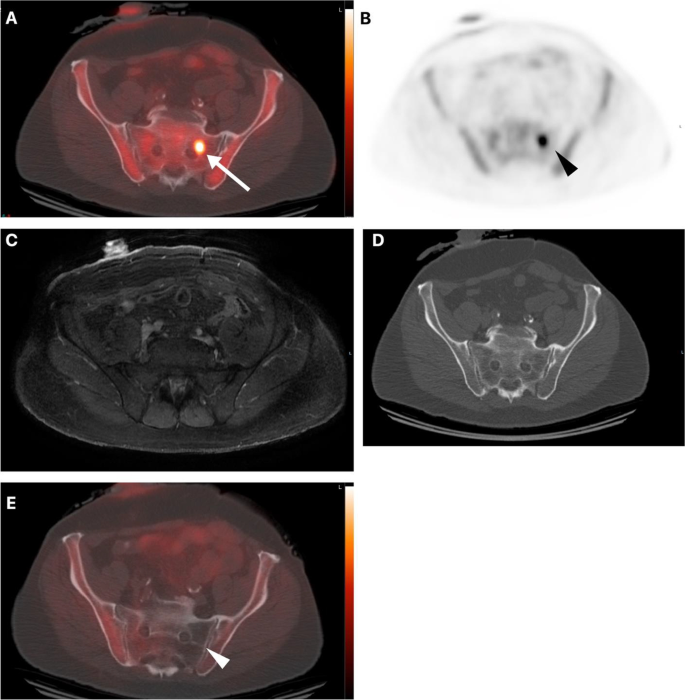

Management Impact Of Metachronous Oligometastatic Disease Identified On 18f Fluciclovine Axumin Pet Ct In Biochemically Recurrent Prostate Cancer Springerlink

True Positive Fluciclovine Pet Ct And False Negative Ct In The Prostate Download Scientific Diagram